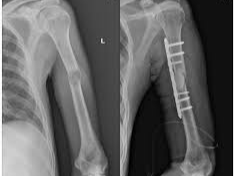

어깨에 골절이 발생하면 일상 전체가 마비되는 기분을 느끼는 것도 무리는 아닙니다. 특히 쇄골, 상완골 근위부, 견갑골 부위에 골절이 생기면 수술이 필요하며, 수술 이후의 재활과 물리치료는 단순히 통증을 없애는 것을 넘어, 관절 가동 범위의 회복과 장기적인 기능 정상화를 위한 핵심 단계입니다. 또한 어깨 골절 수술 이후 본격적으로 시작되는 재활 치료와 도수치료의 현실적인 문제는 ‘비용’과 ‘보험 적용 여부’입니다.

- 수술비: 어깨 골절 수술은 대부분 보장